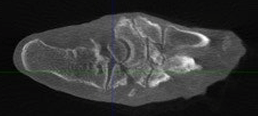

Charcot foot is a complex foot deformity involving subluxations and dislocations and fractures of the foot. It is most commonly seen in patients with uncontrolled Diabetes or other neurological deficiencies. When the nerves to the foot and ankle are not working properly, the blood vessels may increase blood flow to the bones, causing the bones and joints to get weaker, leading to collapse of the joints and bones. The foot may become flat and deformed and develop bone prominences that can become painful and cause open wounds.

Traditional X-Ray can not give the physician the amount of information needed to access the complex midfoot and rearfoot joints in early stages of Charcot. MRI images will show inflammation in the bones, yet make it more difficult to address the spatial orientation of the bones and joints as compared to the weight bearing CT scan.

It is critical to diagnose Charcot deformity in its early stages in order to reduce the chance of significant collapse or fractures. Early diagnosis is best done with CT imaging. The pedCAT weight bearing in office CT system gives the treating physician a 3-dimensional view of the orientation of the joints. It will also show the difference in the stages of Charcot foot. This is important as each stage is treated differently.